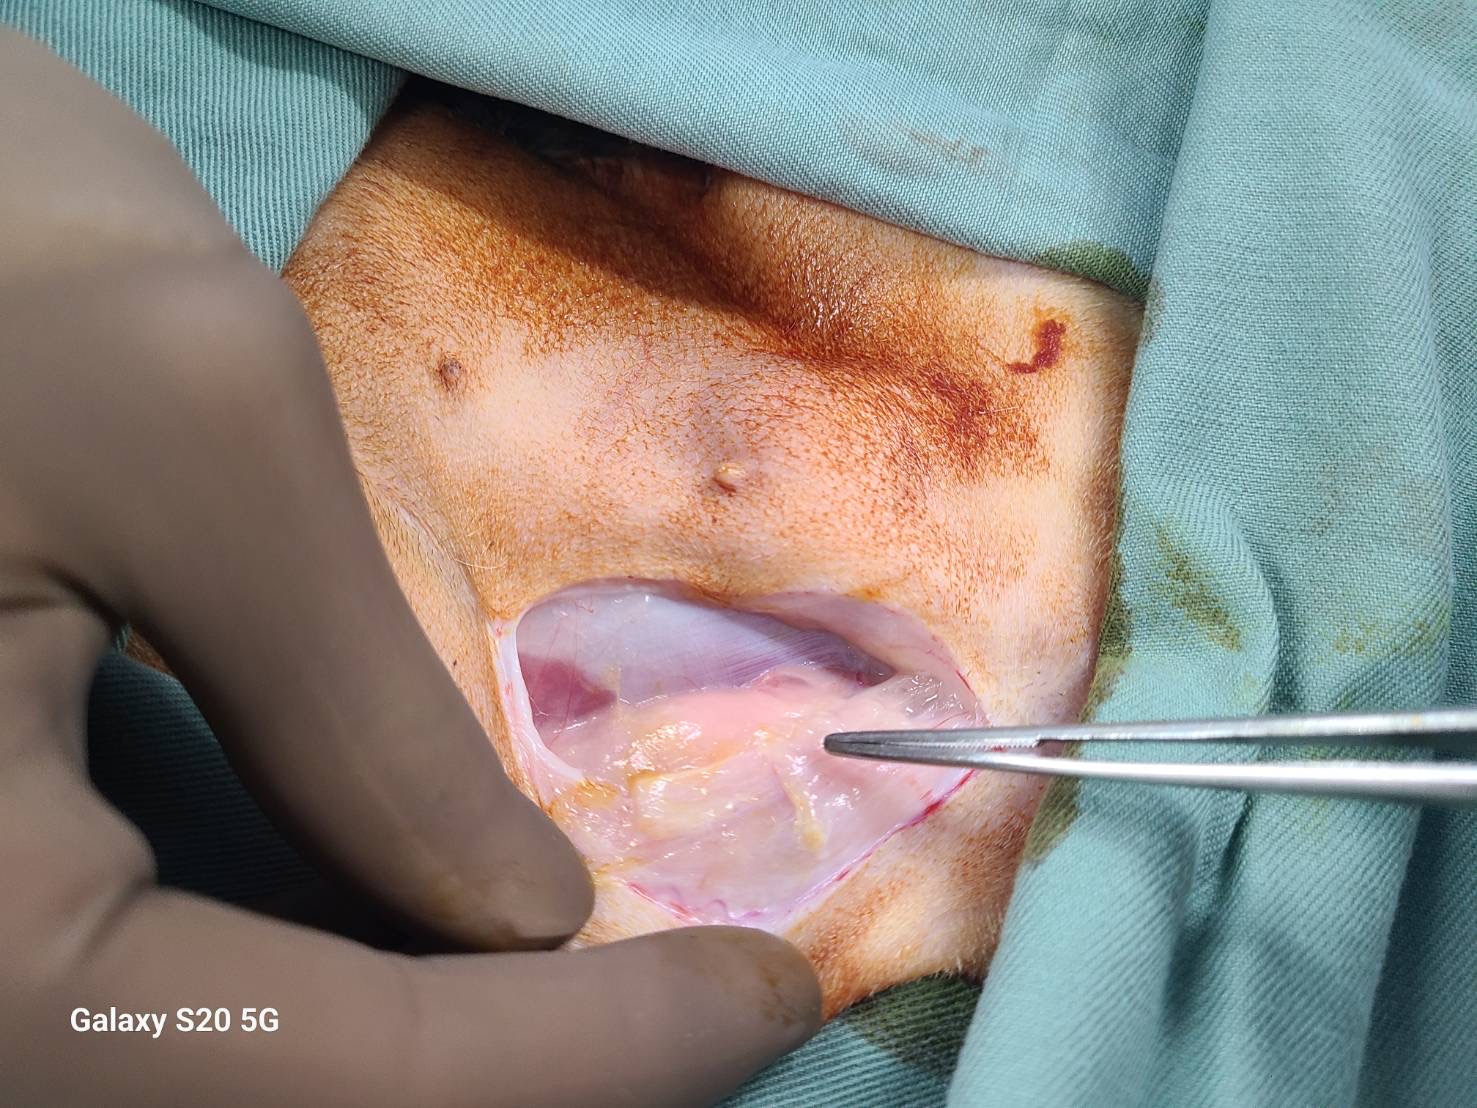

写真